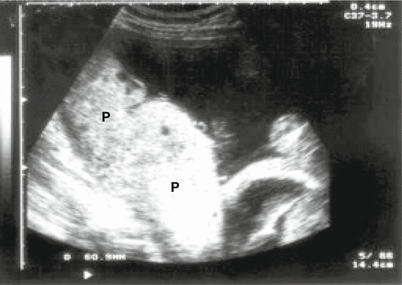

Fig. 15.1

Ultrasound image of a placenta (P) with a thickness of 50 mm (thickened), showing placental involvement in a case of congenital toxoplasmosis